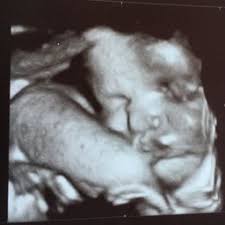

Week 34 Of Pregnancy Symptoms Baby S Development

Week 34 Of Pregnancy Symptoms Baby S Development from soteria.co.nz